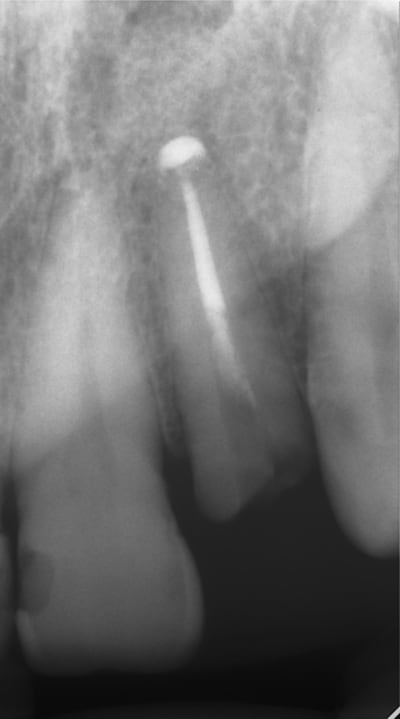

En dessous il y a des photos, dans une on voit (troisième) qu il n y a pas de resorption de l´os après 14 ans, ce que l´on voit c´est l´os très fin condensé sur l´implant.

Le premier photo c´est une erreur parce que le périoste est blessé et les foret "trop" grands.